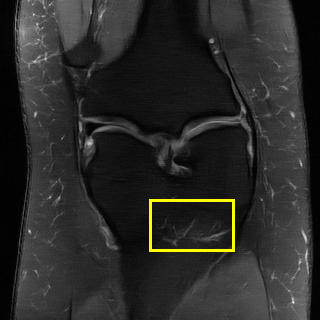

Edge preserving has always been a crucial concern in the design of reconstruction models. To improve the quality of reconstructed images and preserve image edges, some works suggested introducing edge priors in the original restoration problem to preserve image edges [4, 34]. However, they will suffer from complicated algorithm design and time-consuming training processes. Recently, some more efficient methods have been proposed to use edge maps as external guidance for image restoration. For example, Yang et al. [48] used off-the-shelf edge detectors to extract image edges from the degraded images. Fang et al. [12] predicted image edges by constructing an edge reconstruction network. Huang et al. [18] designed a novel dual discriminator GAN framework for solving fast multi-channel MRI, in which one GAN network is built for edge information enhancement. Inspired by these methods, we also consider introducing image edge prior as external guidance to MRI reconstruction since 1) image edges are prominent and distinguishable features in MRI (see Fig. 1), which can serve as a good guide to the model to recover high-frequency details; 2) the ground truth edges can be easily fetched via ordinary edge extraction operators, like Canny, Sobel, and Prewitt, which means that the edge maps can be learned in a data-driven manner. However, how to effectively utilize image edge priors to guide image reconstruction still remains a challenge. In some methods, edge information was simply concatenated with the input image and passed to the next stages. Though this is a simple way to utilize the edge priors, it may not give full play to the guiding role of the edge priors. Therefore, in this work, we want to explore a more efficient and effective mechanism to fully take advantage of image edge priors.

(a)

(b)

(c)

fastMRI is a large-scale MR dataset jointly established by Facebook AI Research and NYU Langone Health. It provides both knee and brain datasets for evaluation. In our work, we use the multi-coil knee dataset, which was acquired on three clinical 3T systems or one clinical 1.5T system using a 15-channel knee coil array. The dataset includes data from two pulse sequences, yielding coronal proton-density weighting with (PDFS) and without (PD) fat suppression. As is shown in Fig. 1, PD images usually contain more structural and prominent edge features than PDFS images, which suggests that it is more challenging to use edge guidance on PDFS datasets. Therefore, we explore the effectiveness of EAMRI on these two modalities. Following [13], for both PD and PDFS knee datasets, we separately filter out 227 volumes (8332 slices) for training and 24 volumes (1665 slices) for testing. The dataset is centrally cropped to .